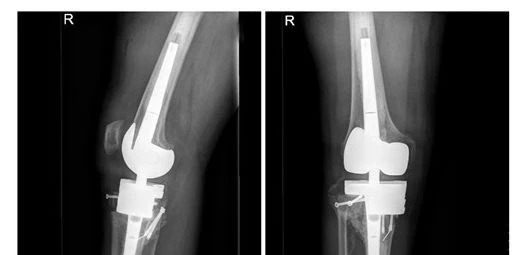

8月22日,关振鹏主任带领骨关节团队为陈先生首先实施了右下肢关节置换手术。手术历时近3个小时,非常成功。手术的成功让陈先生获得了与原来等长并且没有内翻畸形的右下肢,术后恢复良好。

膝关节置换术后